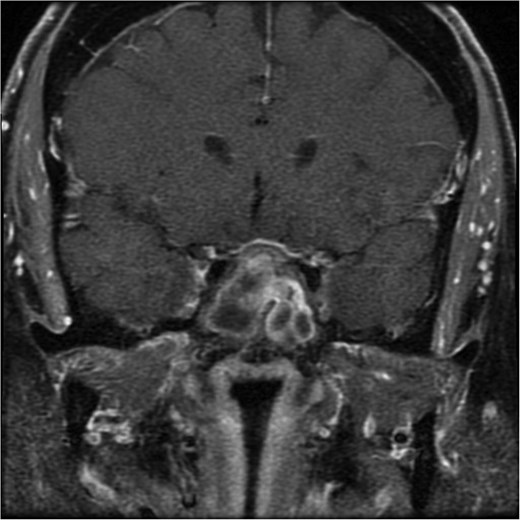

A sagittal brain MRI reveals the same mass with superior extension to the sellar and suprasellar regions. The lesion is exerting a compression to the optic chiasm. The mass effect extends posteriorly toward the clivus, with irregular margins indicating invasive potential. Adjacent structures like the pituitary stalk appear to be displaced.

She underwent endoscopic trans-sphenoidal debulking of the suprasellar lesion (Figs 3 and 4). Postoperatively, the patient developed complications, including diabetes insipidus and panhypopituitarism, requiring levothyroxine and corticosteroid replacement therapy. Histopathology revealed a diagnosis of high-grade primary central nervous system (CNS) B-cell lymphoma. Microscopic analysis showed sheets of atypical lymphoid cells with high mitotic activity. Consequently, the patient was initiated on rituximab and high-dose methotrexate (HD-MTX). Nevertheless, methotrexate was terminated due to the onset of acute kidney injury. Given the patient's intolerance to further HD-MTX, nivolumab was commenced based on PD-L1 expression. While there was partial symptom relief, the tumor response was inadequate. Therefore, the patient underwent whole-brain radiotherapy with a boost to the pituitary region, receiving a total dose of 45 Gy over 25 fractions. This treatment was effective, though she experienced alopecia, mild nausea, blurred vision, headaches, and severe vulvar itching.